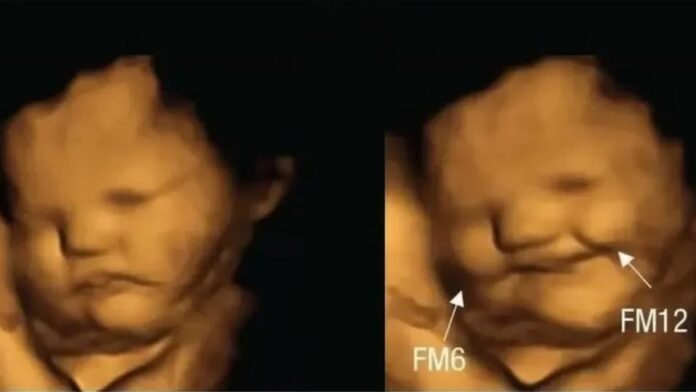

Baladweyne ( Radio Beerlula )-Dhowaan ayay ahayd , markii haweeney xaamilo ah oo aaday isbitaal dowladeed oo ku yaala Hindiya si ay u marto tijaabada Kombiyuutarka Uur-kujirta ee ultrasound, dhakhaatiirtu ay ku arkeen Ilmaha ku jira caloosha haweenayda.

Laakiin mucjisada la arkay ayaa ah wax u eg ilmo kale oo ku sii dhex jira caloosha ilmaha ay uurka ku sido.

Haweenaydan oo kasoo jeeda degmada Buldhana ee dalka Hindiya oo u aaday isbitaalka si xaaladeeda ula socoto ayaa dhakhaatiirta inta baaritaanka ay ku wadeen ku ogaadeen inuu ku dhexjiro ilmo kale oo aad u yar.